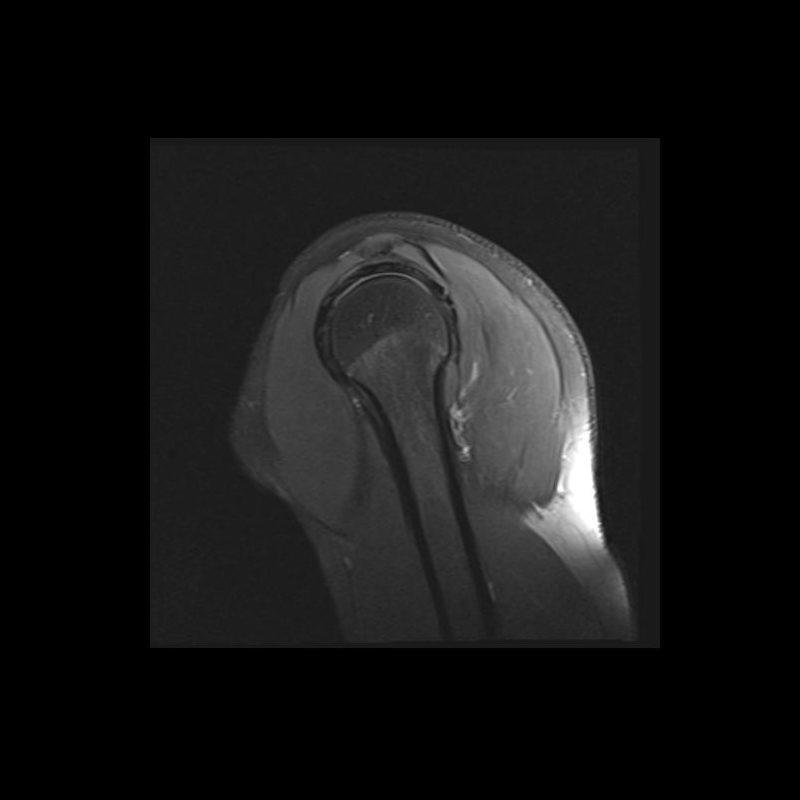

Shoulder MRI Anatomy